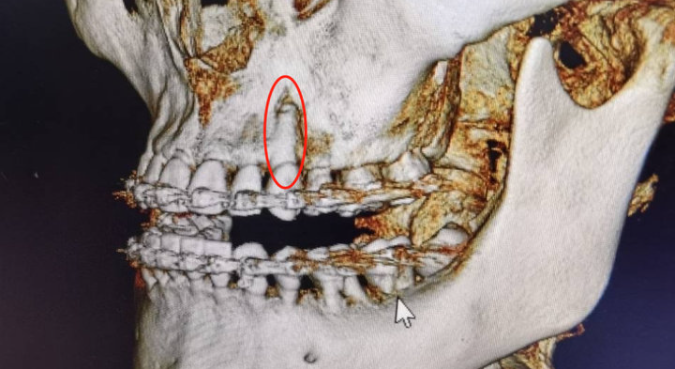

《正畸案例41:正畸中的骨开裂与骨开窗》

《正畸案例41:正畸中的骨开裂与骨开窗》